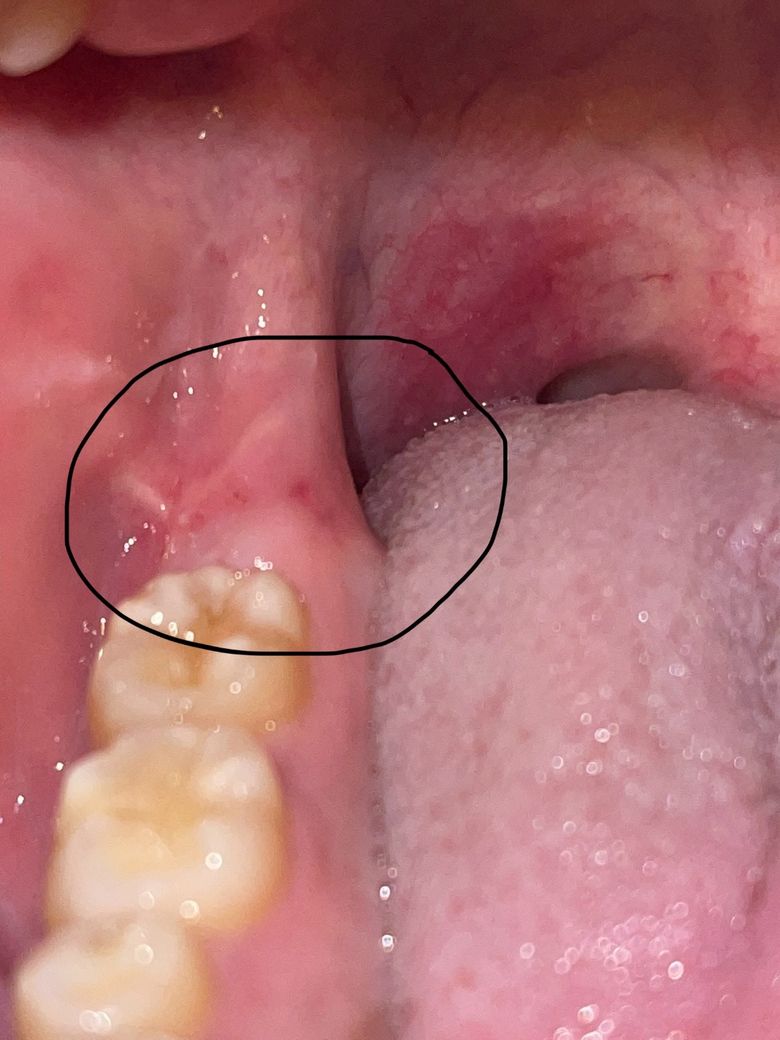

혹시 구강암일까요? 사진 있습니다.

어제부터 뜨거운 음식 먹을 때 저 부위가 아파서 보니까 빨갛게 되어 있더라고요 어제 딱딱한 음식을 먹긴 했는데 그것 때문인지는 모르겠습니다.

아직 아픈지는 하루 밖에 안됐지만 걱정 돼서 질문해봅니다

치주염일 가능성이 높아보이며 구강암일 가능성은 전혀 없기 때문에 걱정하지 않으셔도 되겠습니다.